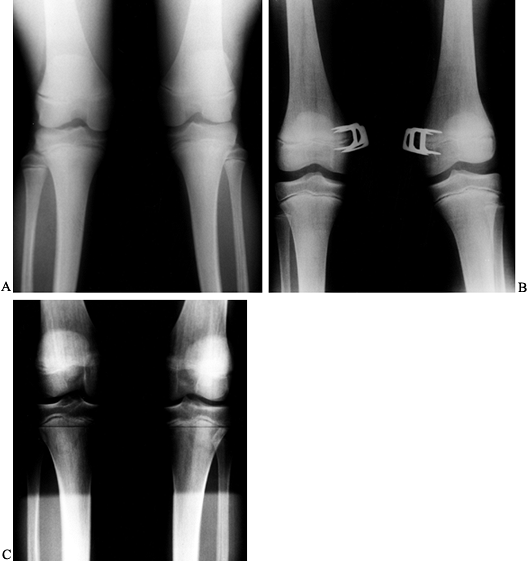

![]() |

Figure 169.14. A: A 14-year-old boy with persistent severe physiologic genu valgum. B:

Standing AP radiograph of both lower extremities demonstrates a valgus deformity in the distal femora and proximal tibiae. Observe the physeal widening at the proximal tibial physes. A metabolic evaluation was normal. C: Postoperative radiograph of the left knee after stapling of the medial aspect of the distal femoral and proximal tibial epiphyses shows the three staples used to bracket each epiphysis. D: Lateral radiograph. E: Standing radiograph of both knees 9 months postoperatively shows excellent correction of the genu valgum deformities. F: On a standing radiograph 6 months after staple removal, physiologic alignment is being maintained. G: Clinical photograph. |